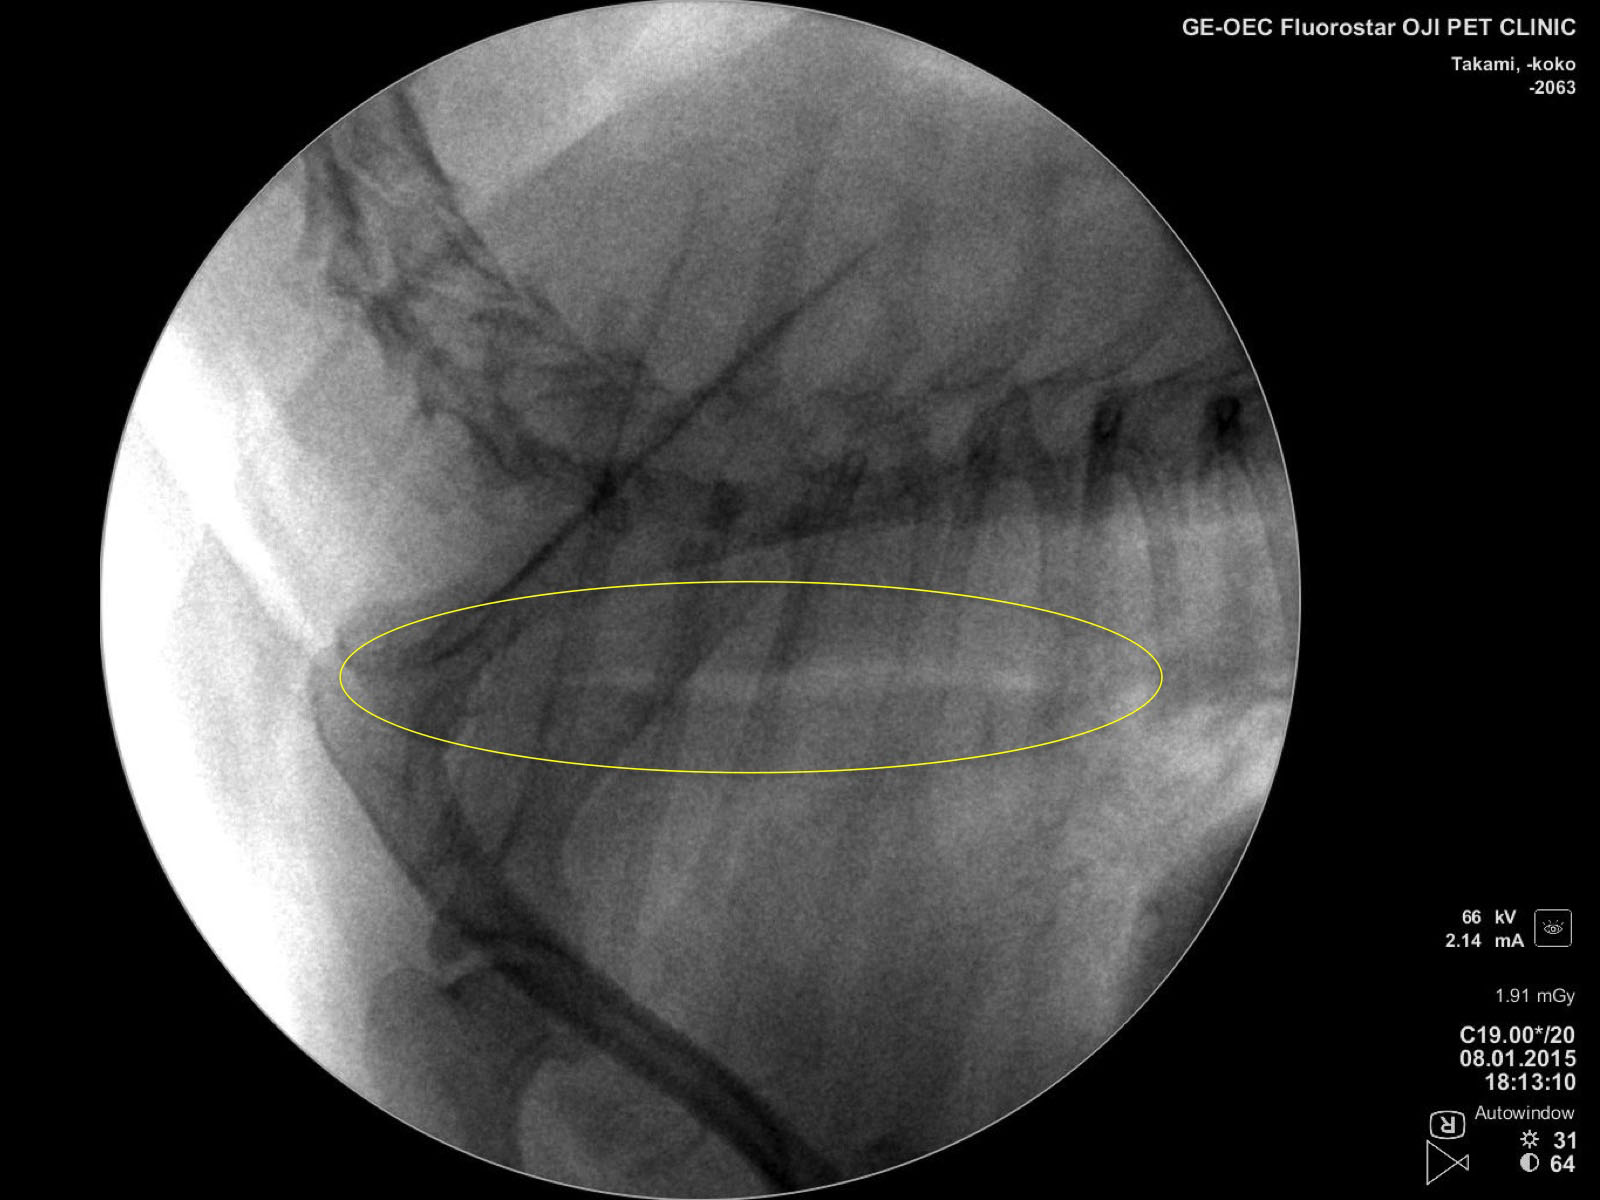

当院では外科用X線診断装置(Cアーム)を導入しました。

Cアームは透視画像により手術技術補助や診断に活用することが出来ます。

ご飯を食べるとすぐに吐いてしまうとのことで来院されました。

問診をして食道の動きの問題であることが疑われたのでバリウムという造影剤を飲ませてCアームで撮影してみると・・・

上のような画像が得られました。

赤丸で囲われているところに黒い造影剤が溜まっているのが分かります。

この所見は巨大食道症という病気でみられます。

この症例は巨大食道症により食道が拡張し、赤丸のところに食べたもの・飲んだものが溜まって吐いてしまっていたのです。

夜眠る事ができないくらい咳がひどいとのことで来院。 Cアームで撮影すると、

頚部から胸腔内の気管が潰れ、虚脱している様子が分かります。

動的に評価する事で吸気、呼気の気管の状態をしっかりと把握することができます。